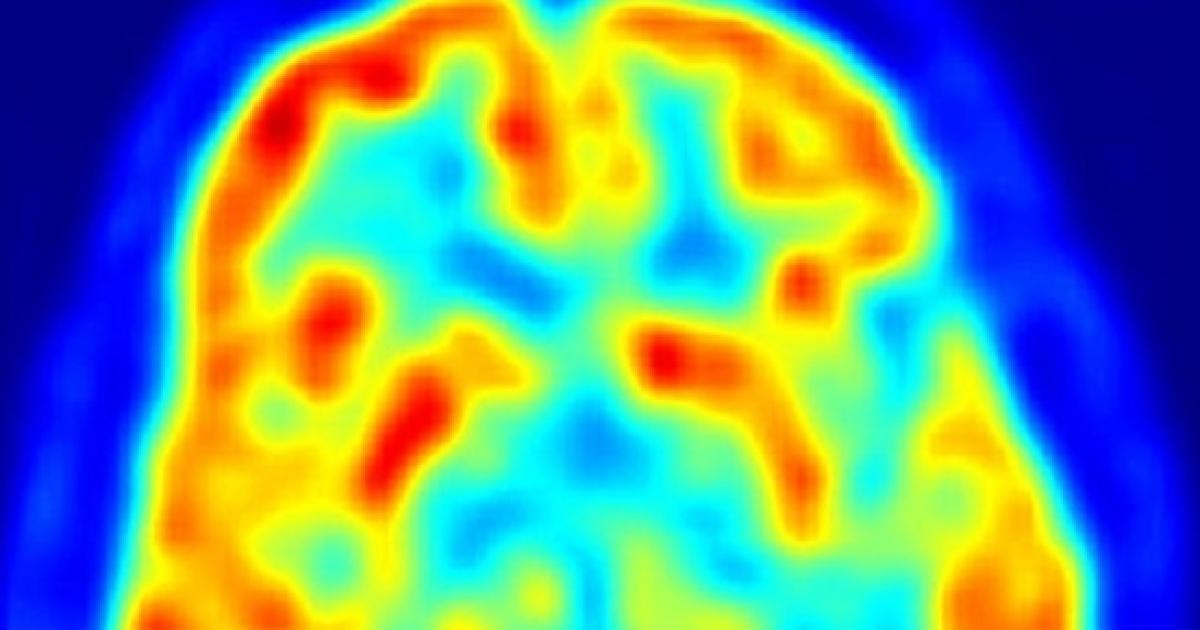

Brain tumors can affect brain function if they grow large enough to press on surrounding nerves, blood vessels and tissue. Symptoms of brain tumors vary depending on the type, size, and exact location in the brain. While it is true that radiation and chemotherapy are used more often for malignant, residual or recurrent tumors.

These symptoms are as variable as. Symptoms include headaches, nausea, and coordination problems. Brain tentacles comprised of bruce lamont (bloodiest), dave witte (publicist uk, circle of animals) and aaron dallison (keelhaul), brain tentacles create a twisted sound like no other. Brain tumor symptoms may include headaches, seizures, paralysis, loss of muscle control, and memory problems.